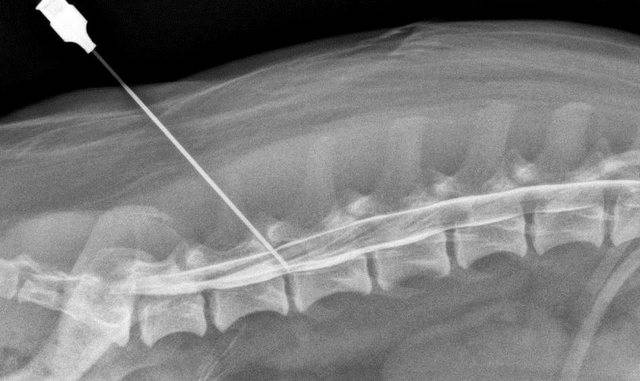

- Собственно процедура. После того как анестезия начнет действовать, специалист берет толстую длинную иглу (длина 10 см). Этой иглой он прокалывает пораженную зону и вводит лекарство. Препараты вводятся по специальной схеме, в определенные точки вокруг патологического очага.

Перед процедурой пациента обследуют, а затем обозначают и подготавливают места инъекций. Поскольку игла будет введена достаточно глубоко – сначала полностью, а затем – на 2-3 см, проводится местная анестезия прилегающих тканей. Однако, возможно, пациенту придется претерпеть несильную боль или дискомфорт. Положение больного для проведения процедуры — лежа на животе или сидя, в зависимости от расположения и вида грыжи.

Врач перед введением медикаментов должен прощупать позвоночник и саму грыжу, чтобы понять, в какие места проводить инъекцию. Введение лекарственных средств происходит в нескольких сантиметрах от отростков позвонков. Анестезиолог делает несколько инъекций в ряд параллельно позвоночнику через каждые полтора сантиметра. Пациент должен слушать врача и при необходимости поворачиваться так, чтобы игла вошла правильно. Чаще всего выбирается шесть точек по обе стороны позвоночного столба, за счет чего каждая ветка боли «отключается».